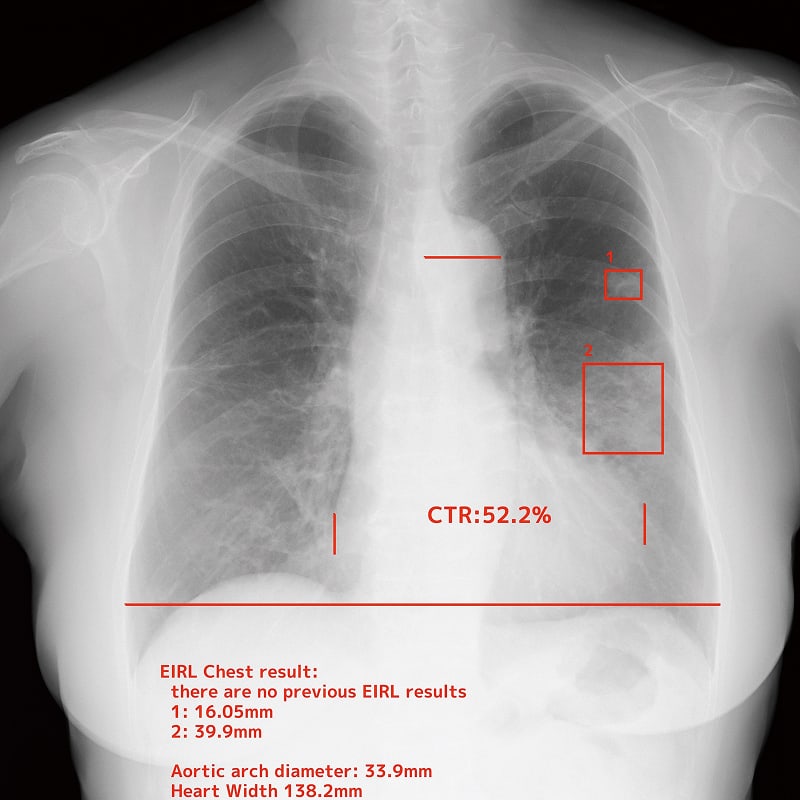

Chest nodule detection support technology that makes an effective diagnosis possible

EIRL Chest Nodule supports the interpretation process by identifying findings suggestive of lung nodules from chest X-rays that are larger than 5 mm and smaller than 30 mm. The sensitivity of the specialized-radiologist and the non-specialized radiologist interpreting the images with the software increased by 9.9% and 13.1 % respectively, suggesting an improvement in diagnostic accuracy.